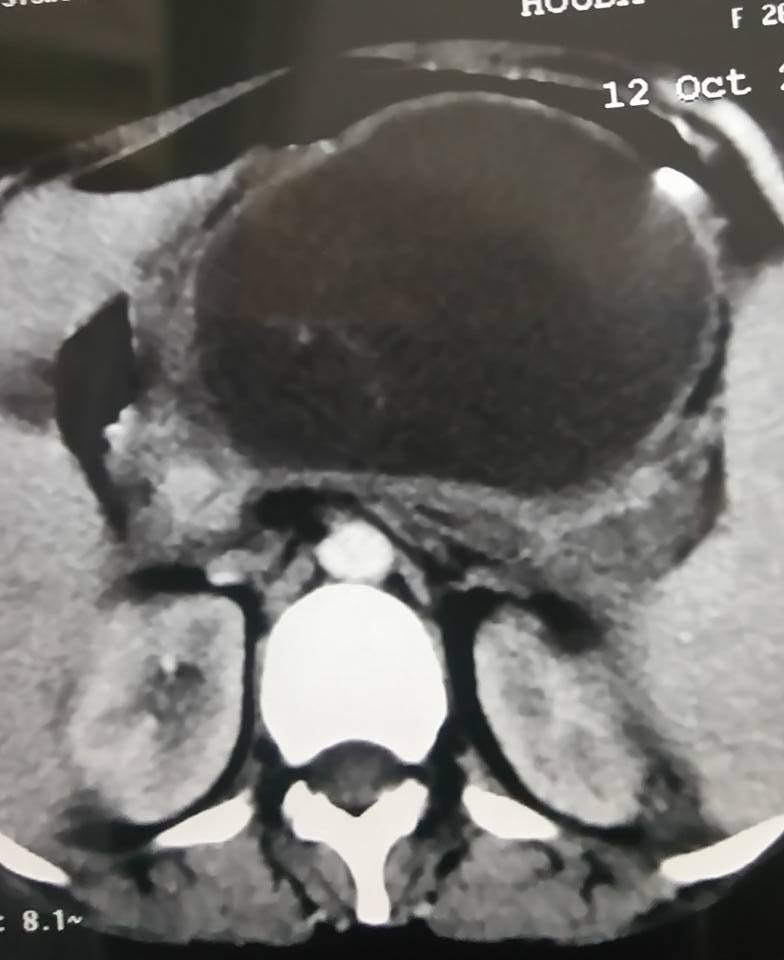

إستخدام المنظار الجراحي لإجراء عملية إستئصال المرارة ثم تفريغ وتنظيف كيس كبير صديدي بالبنكرياس ناتج عن مضاعفات إلتهاب حاد بالبنكرياس نتيجة مرور حصوات صغيرة بالقناة المرارية. والحمد لله رب العالمين. A 26 y old female patient presented with history of...